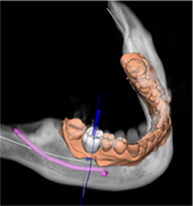

B.绘制下颌神经管

E.软件上修复体设计

F.选择牙位添加种植体

G.选择合适的导环全程或者定位完成植体设计